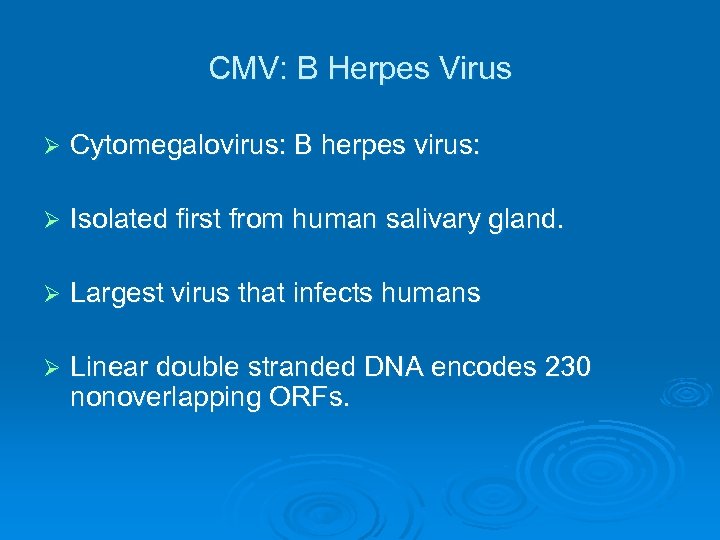

CMV: B Herpes Virus Ø Cytomegalovirus: B herpes virus: Ø Isolated first from human salivary gland. Ø Largest virus that infects humans Ø Linear double stranded DNA encodes 230 nonoverlapping ORFs.